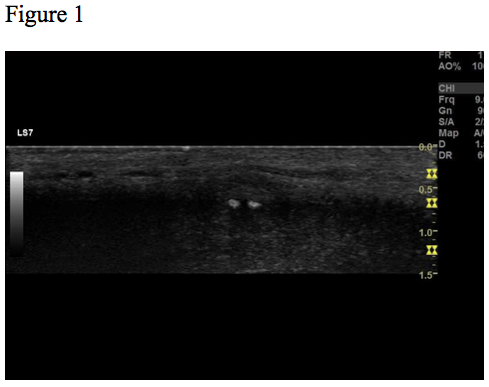

Ultrasound examination revealed a 0.6 x 0.4 cm hypoechoic lesion with two hyperechoic spots inside (Fig. 1-3). The lesion was well-circumscribed, located subcutaneously. On elastography, the lesion appeared hard relative to the surrounding tissue (Fig. 4). The lesion was without flow on colour Doppler.

Figure 1, 2, 3 and 4 show the same hypoechoic lesion, a Peyronie’s plaque, in the penile connective tissue. The lesion has a well-defined circumference.